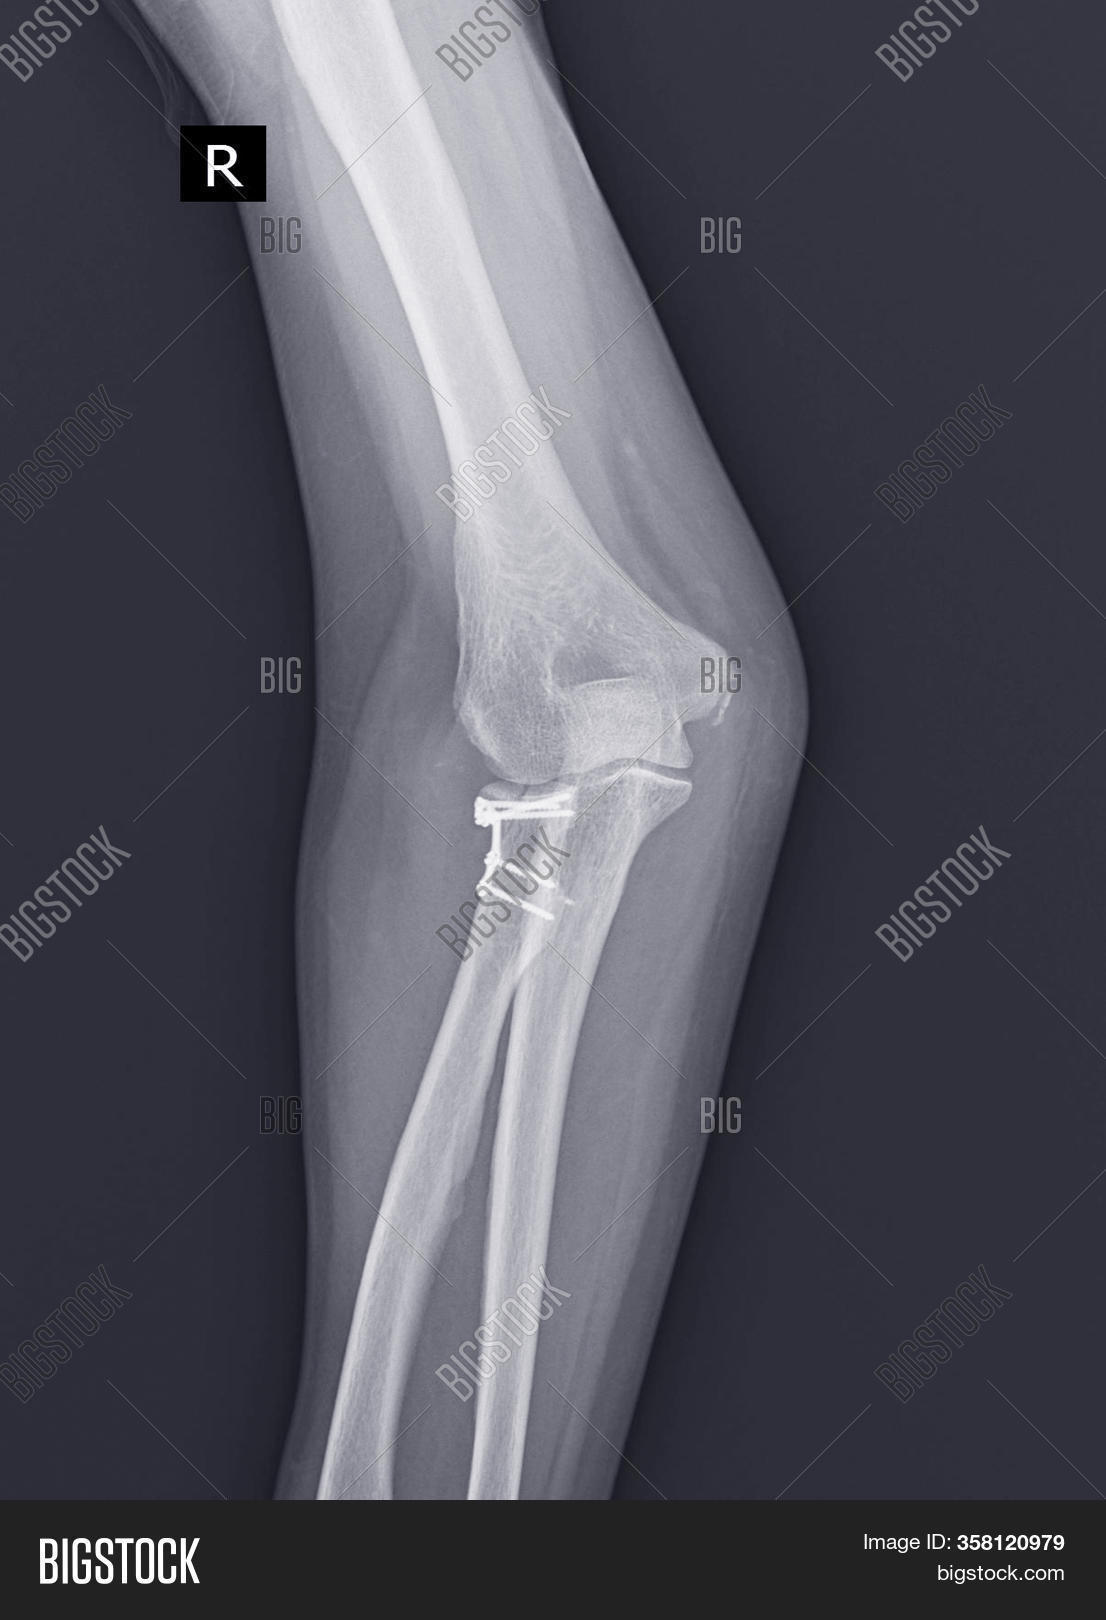

From www.bigstockphoto.com

Elbow Joint XRay Image & Photo Bigstock X Rays Of Elbow Joint The elbow series is a set of radiographs taken to investigate elbow joint pathology, often in the context of trauma. An x ray image of the elbow joint provides information for assessment, evaluation and diagnosis of elbow joint disease process or injury, such as fracture and gives. On “anatomical parts” you can choose between two types of labels: Check the. X Rays Of Elbow Joint.